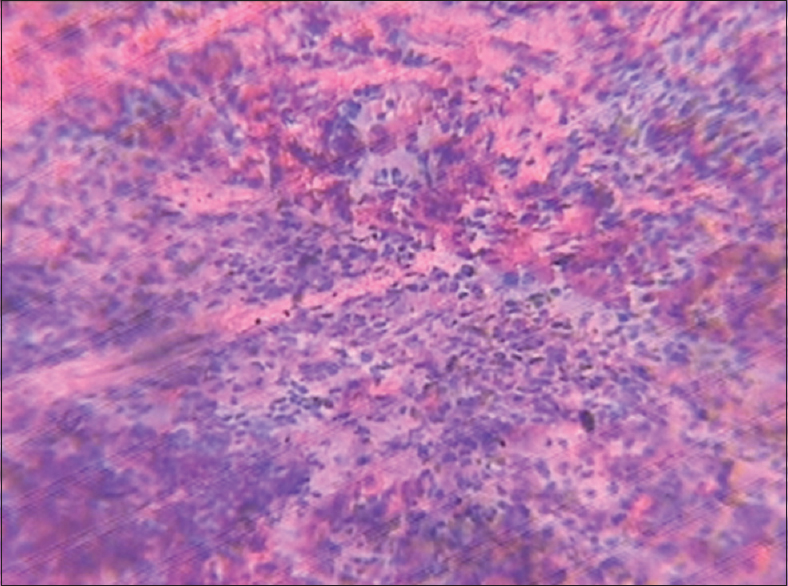

Figure 5: Spleen (control group)